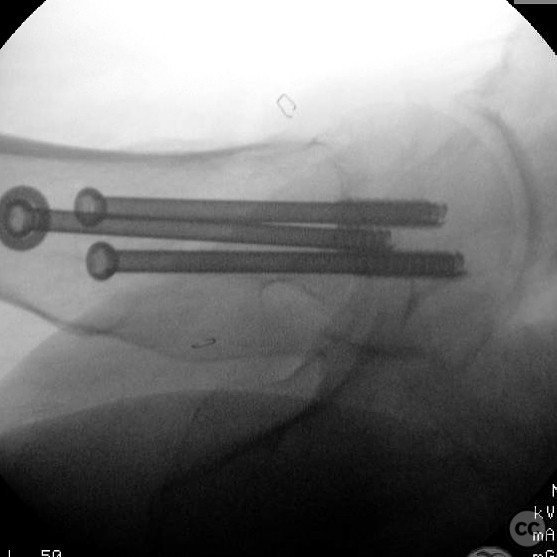

Clinical and radiological findings:  A 62-year-old male presented following a fall from standing height, resulting in a displaced subcapital femoral neck fracture. The patient has a complex medical history including substance abuse (methamphetamine and cocaine), cirrhosis, diabetes, and open draining foot wounds. Radiographs confirmed a displaced femoral neck fracture, classified as AO/OTA 31-B2.

Anatomical surgical approach:  A percutaneous approach was utilized, involving small stab incisions for the insertion of guide wires and cannulated screws. Fluoroscopic imaging was employed to ensure proper alignment and fixation.

Orthopaedic implants used:   Cannulated screws